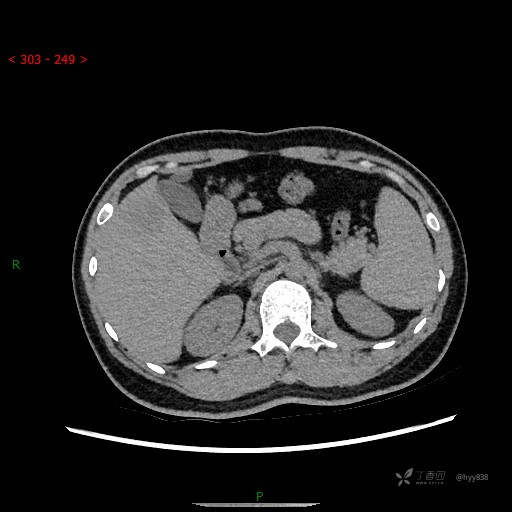

增强动脉期